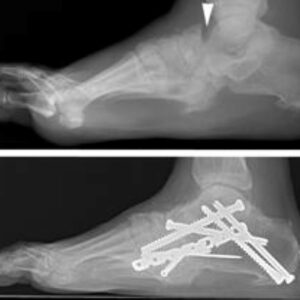

Foot & Ankle Patient informationPilon fractures are a distinct type of injury affecting the lower end of the tibia (shinbone), specifically involving the weight-bearing surface of the ankle joint. These fractures often extend to the fibula, the other bone in the lower leg. Typically resulting from high-impact incidents such as motor vehicle accidents or